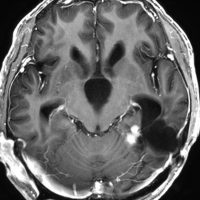

左は8歳時のMRIで,異常所見がありませんでした。左側頭葉に発作時の異常脳波所見が認められ,側頭葉てんかんの診断でカルバマゼピンの投与が開始されました。9歳時に精神症状を呈する発作となりレベチラセタムとゾニザミドが加えられました。右側のMRIは9歳時のものですが異常所見はありませんでした。前後にさまざまな画像が撮影されていましたが脳腫瘍の所見はありませんでした。